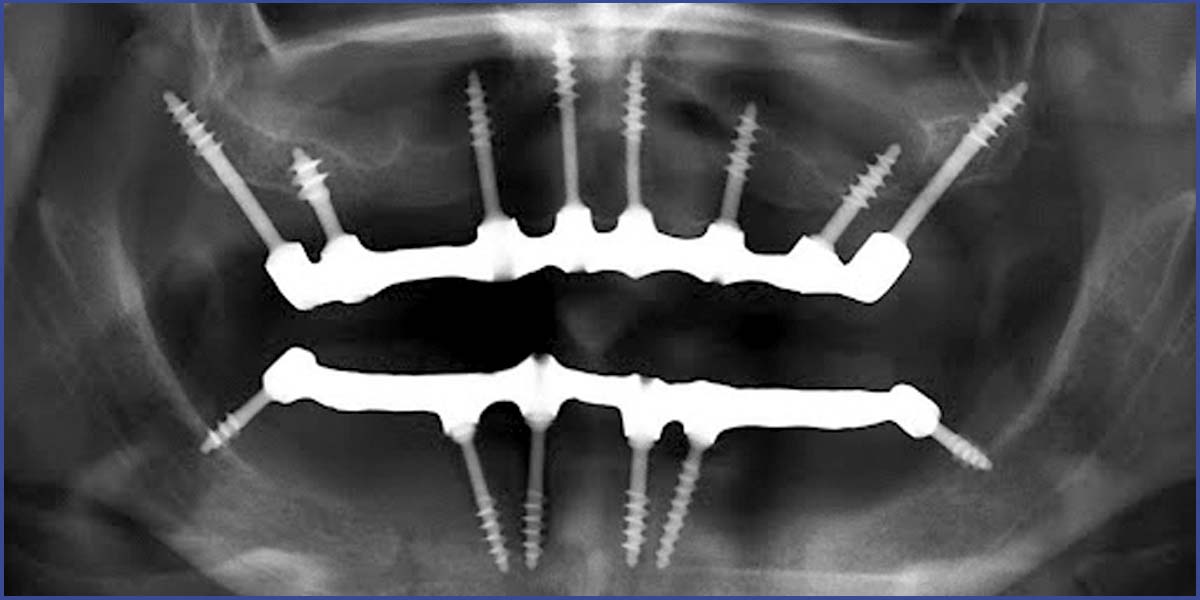

A fog gyökérkezelés egy alapvető fogmentő beavatkozás A konzerváló fogászati ellátás egyik gyakran előforduló „fogmentő” akciója a fog gyökérkezelés. Ez akkor válik szükségessé, amikor megfertőződik és begyullad a foggyökeret alkotó szövet, ami rendkívül érzékeny, miután sűrűn át van szőve idegvégződésekkel. A kezelés célja a gyulladt rész eltávolítása, majd a gyökércsatorna alapos